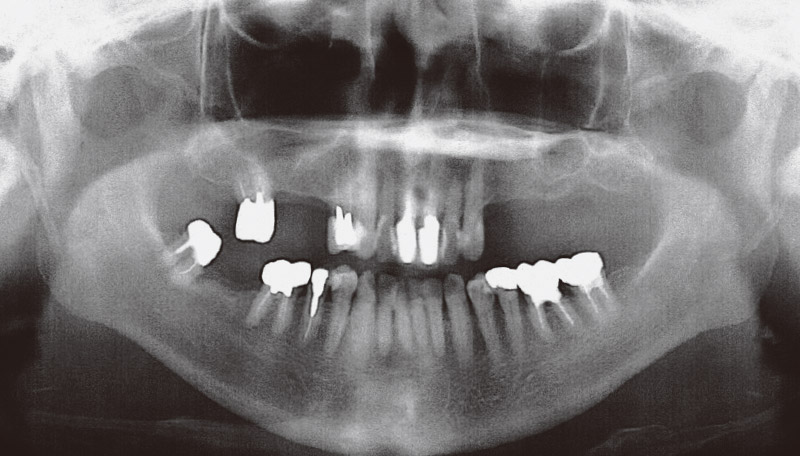

患者は60代女性で、両側上顎臼歯部欠損のため、義歯を使用されていたが、違和感が強く、インプラント治療目的に当科紹介受診した。既往歴に特記事項なく、パノラマX線およびCT像では、両側上顎臼歯部に上顎洞底が拡大し、相対的顎堤萎縮を認めた (図5、6)。

術前シミュレーションとして、デジタルワックスアップを行い、埋入位置を確認し、埋入部既存骨が2~3mmであったため、治療計画として、ボナークを用いた両側サイナスリフト後、待時埋入としてインプラント体を埋入する予定とした。さらに、右側サイナスリフト6か月後にインプラント埋入と同時に左側サイナスリフトを計画していたが、患者希望もあり、右側はサイナスリフト12か月後で左側はサイナスリフト6か月後でインプラント体を埋入することとなった。